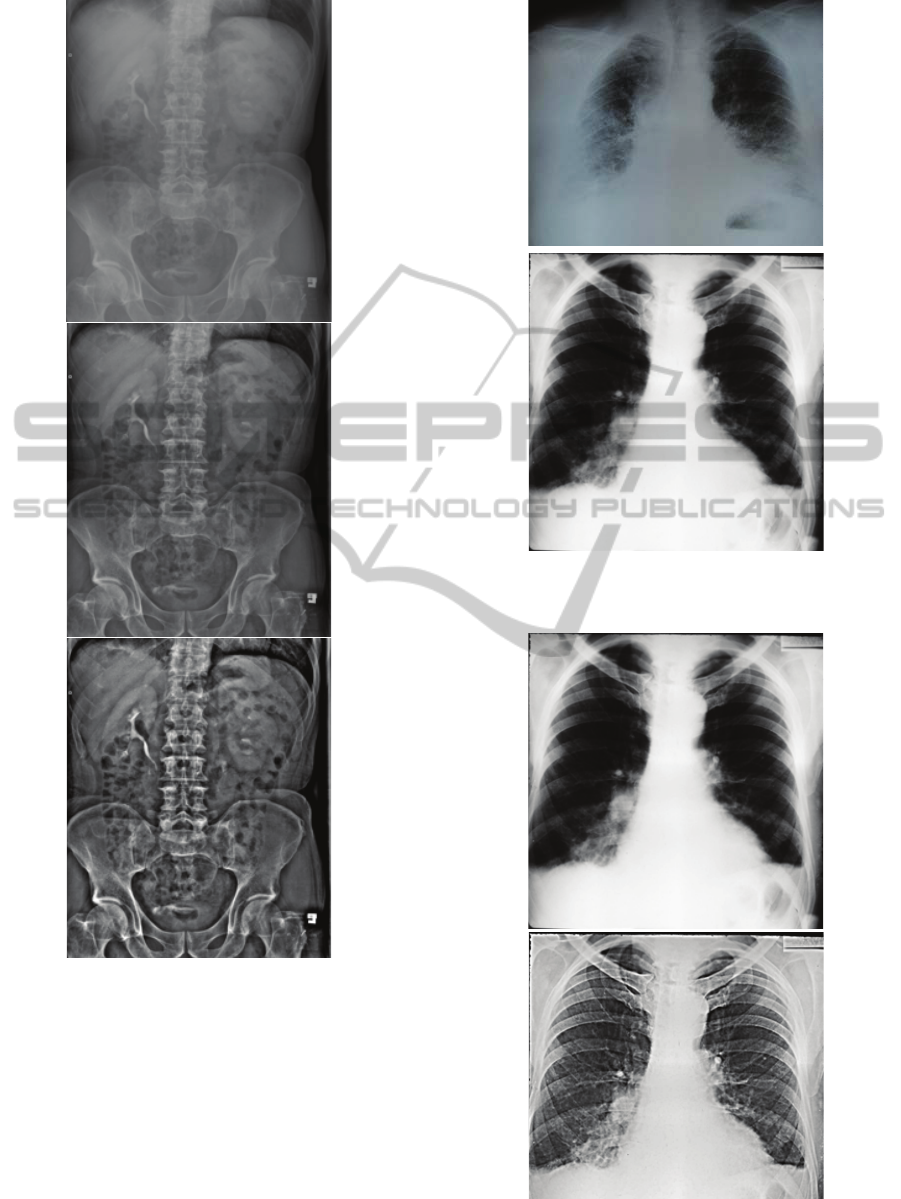

5 IMPLEMENTATION RESULTS

Two classes of digital photo cameras are used for

the development of camera-based scanning devices:

“Compact Super Zoom” (manual mode, 12x optical

zoom, 12 M effective pixels, less than 1% optical

distortion, <300 g) and „Compact” (manual mode,

4x optical zoom, 7 M effective pixels, ~ 1% optical

distortion, ~ 220 g). Cameras of the “Compact Super

Zoom” class have provided much greater

opportunities for developing devices which will

substantially expand the potential applications of the

system. All results described below are based on the

use of devices with this type of camera.